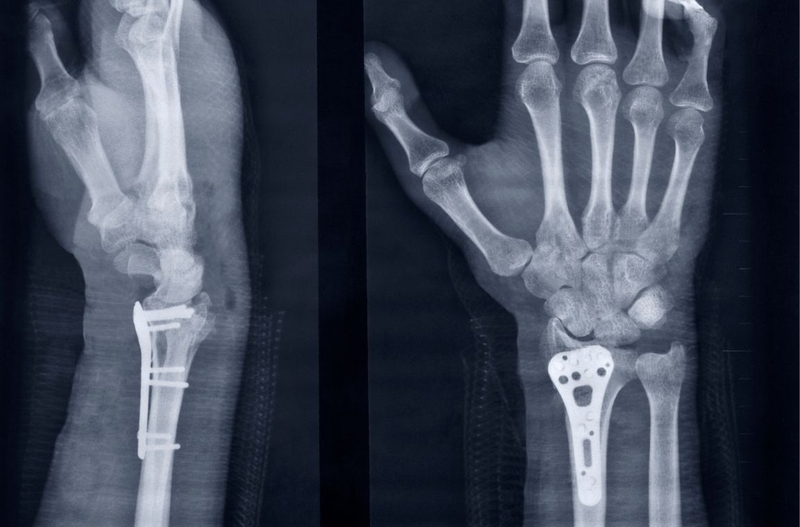

Giống như chụp X quang tay, chụp X quang cổ tay là một kỹ thuật chẩn đoán hình ảnh, không có sự xâm lấn nhưng lại cho ra kết quả khá rõ ràng và chính xác. Đây là căn cứ tin cậy để bác sĩ đánh giá các tổn thương, bất thường hay bệnh lý ở vùng cổ tay của người bệnh như:

Giống như chụp X quang bàn tay, chụp X quang cổ tay là một kỹ thuật xét nghiệm hình ảnh rất đơn giản. Toàn bộ quy trình chụp có thể chỉ diễn ra trong vòng 10 - 15 phút. Người bệnh chỉ cần chờ đợi thêm ít phút để kỹ thuật viên xử lý hình ảnh và chuyển đến cho bác sĩ. Khi thông tin thu được đã đầy đủ, bác sĩ có thể đánh giá và chẩn đoán chính xác các vấn đề bệnh nhân đang gặp phải ở vùng cổ tay. Tuy nhiên, cũng có trường hợp bệnh nhân cần được chụp lại một lần nữa hoặc làm thêm các xét nghiệm hình ảnh khác.